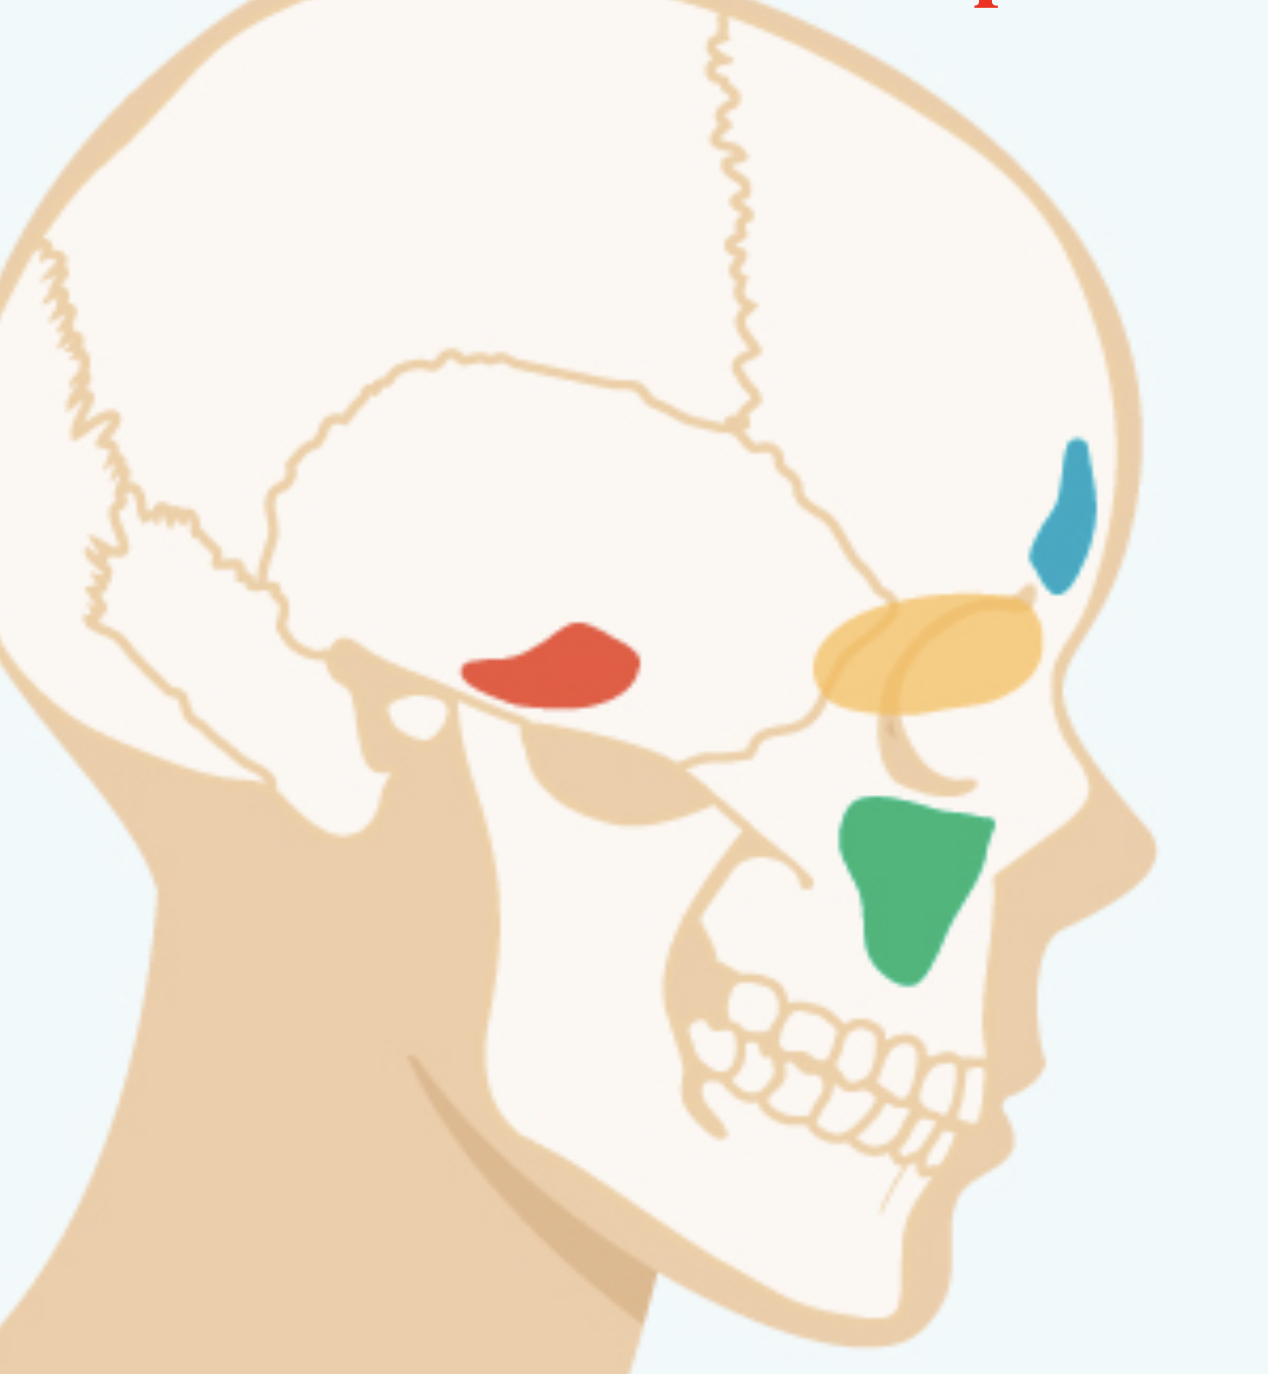

Label the different Sinuses?

Red=Sphenoid Sinus

Green=Maxillary SInus

Yellow= Ethmoid Sinus

Blue= Frontal Sinus